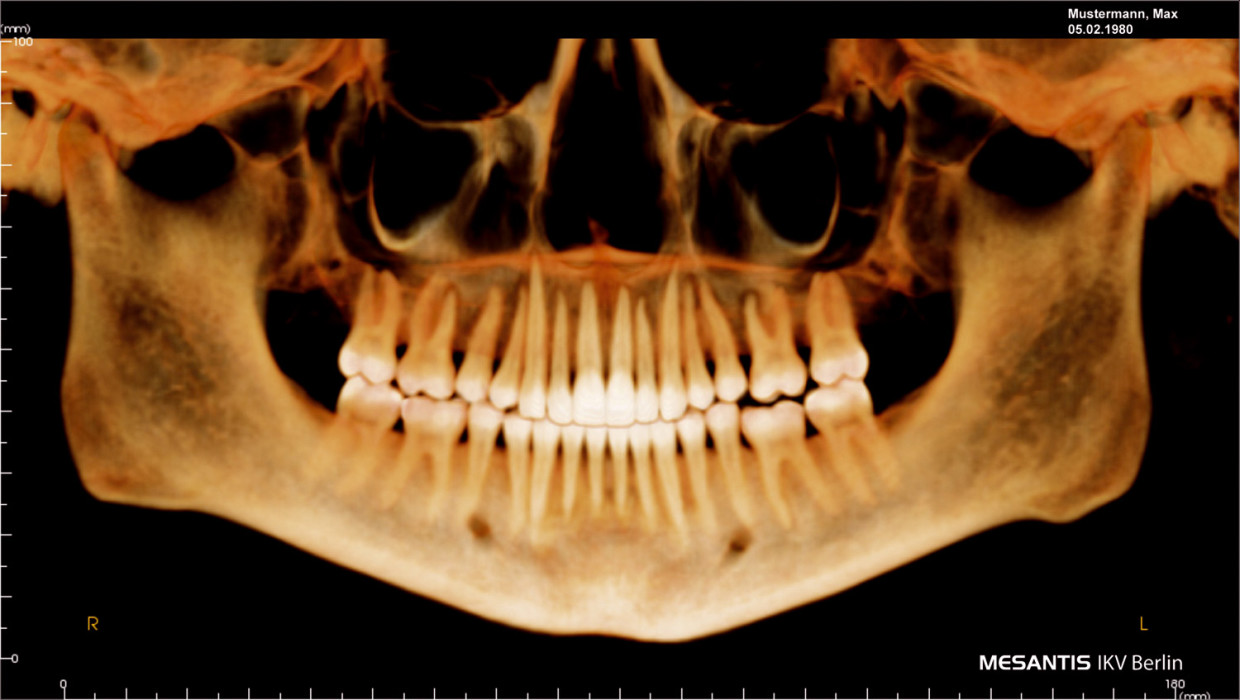

Der Einsatz digitaler Volumentomografie in der Zahnmedizin eröffnet ohne Frage ein breites Spektrum an diagnostischen Möglichkeiten (Abb. 1, 2). Um hierbei jedoch betriebswirtschaftlich sinnvoll agieren zu können, müssen einige wichtige Aspekte berücksichtigt und im täglichen Umgang mit DVTs entsprechend umgesetzt werden. So stellen neben dem großen Investitionsvolumen insbesondere der Datenschutz sowie die Langzeitarchivierung den Praktiker vor große Probleme. Diese Artikeltrilogie befaßt sich mit den positiven als auch negativen Erfahrungen rund um den Einsatz dieser Diagnostikmethode. In Teil 1 widmet sich RA Andreas Straubinger den Anforderungen an die elektronische Archivierung sowie dem Versenden von Patientendaten und Röntgenbildern.

Abb. 1: Darstellung des vestibulären Knochenangebotes im Unterkiefer vor kieferorthopädischer Zahnbewegung. Diese Darstellung ist extrem wichtig für die Kieferorthopädie, da mehr als 70 % der Kinder und Jugendlichen an einem oder mehreren Zähnen vestibulären Knochenverlust vor Expansion des Zahnbogens aufweisen. Abb. 2: Einengung der oberen Atemwege in der Frontalansicht aufgrund ausgeprägter Hyperplasie der Tonsillen (Pfeile). Durch die digitale Volumentomografie werden im Rahmen der kieferorthopädischen Behandlungsplanung bei ca. 20 % der Patienten therapierelevante Befunde im Bereich der oberen Atemwege und Nebenhöhlen gefunden.